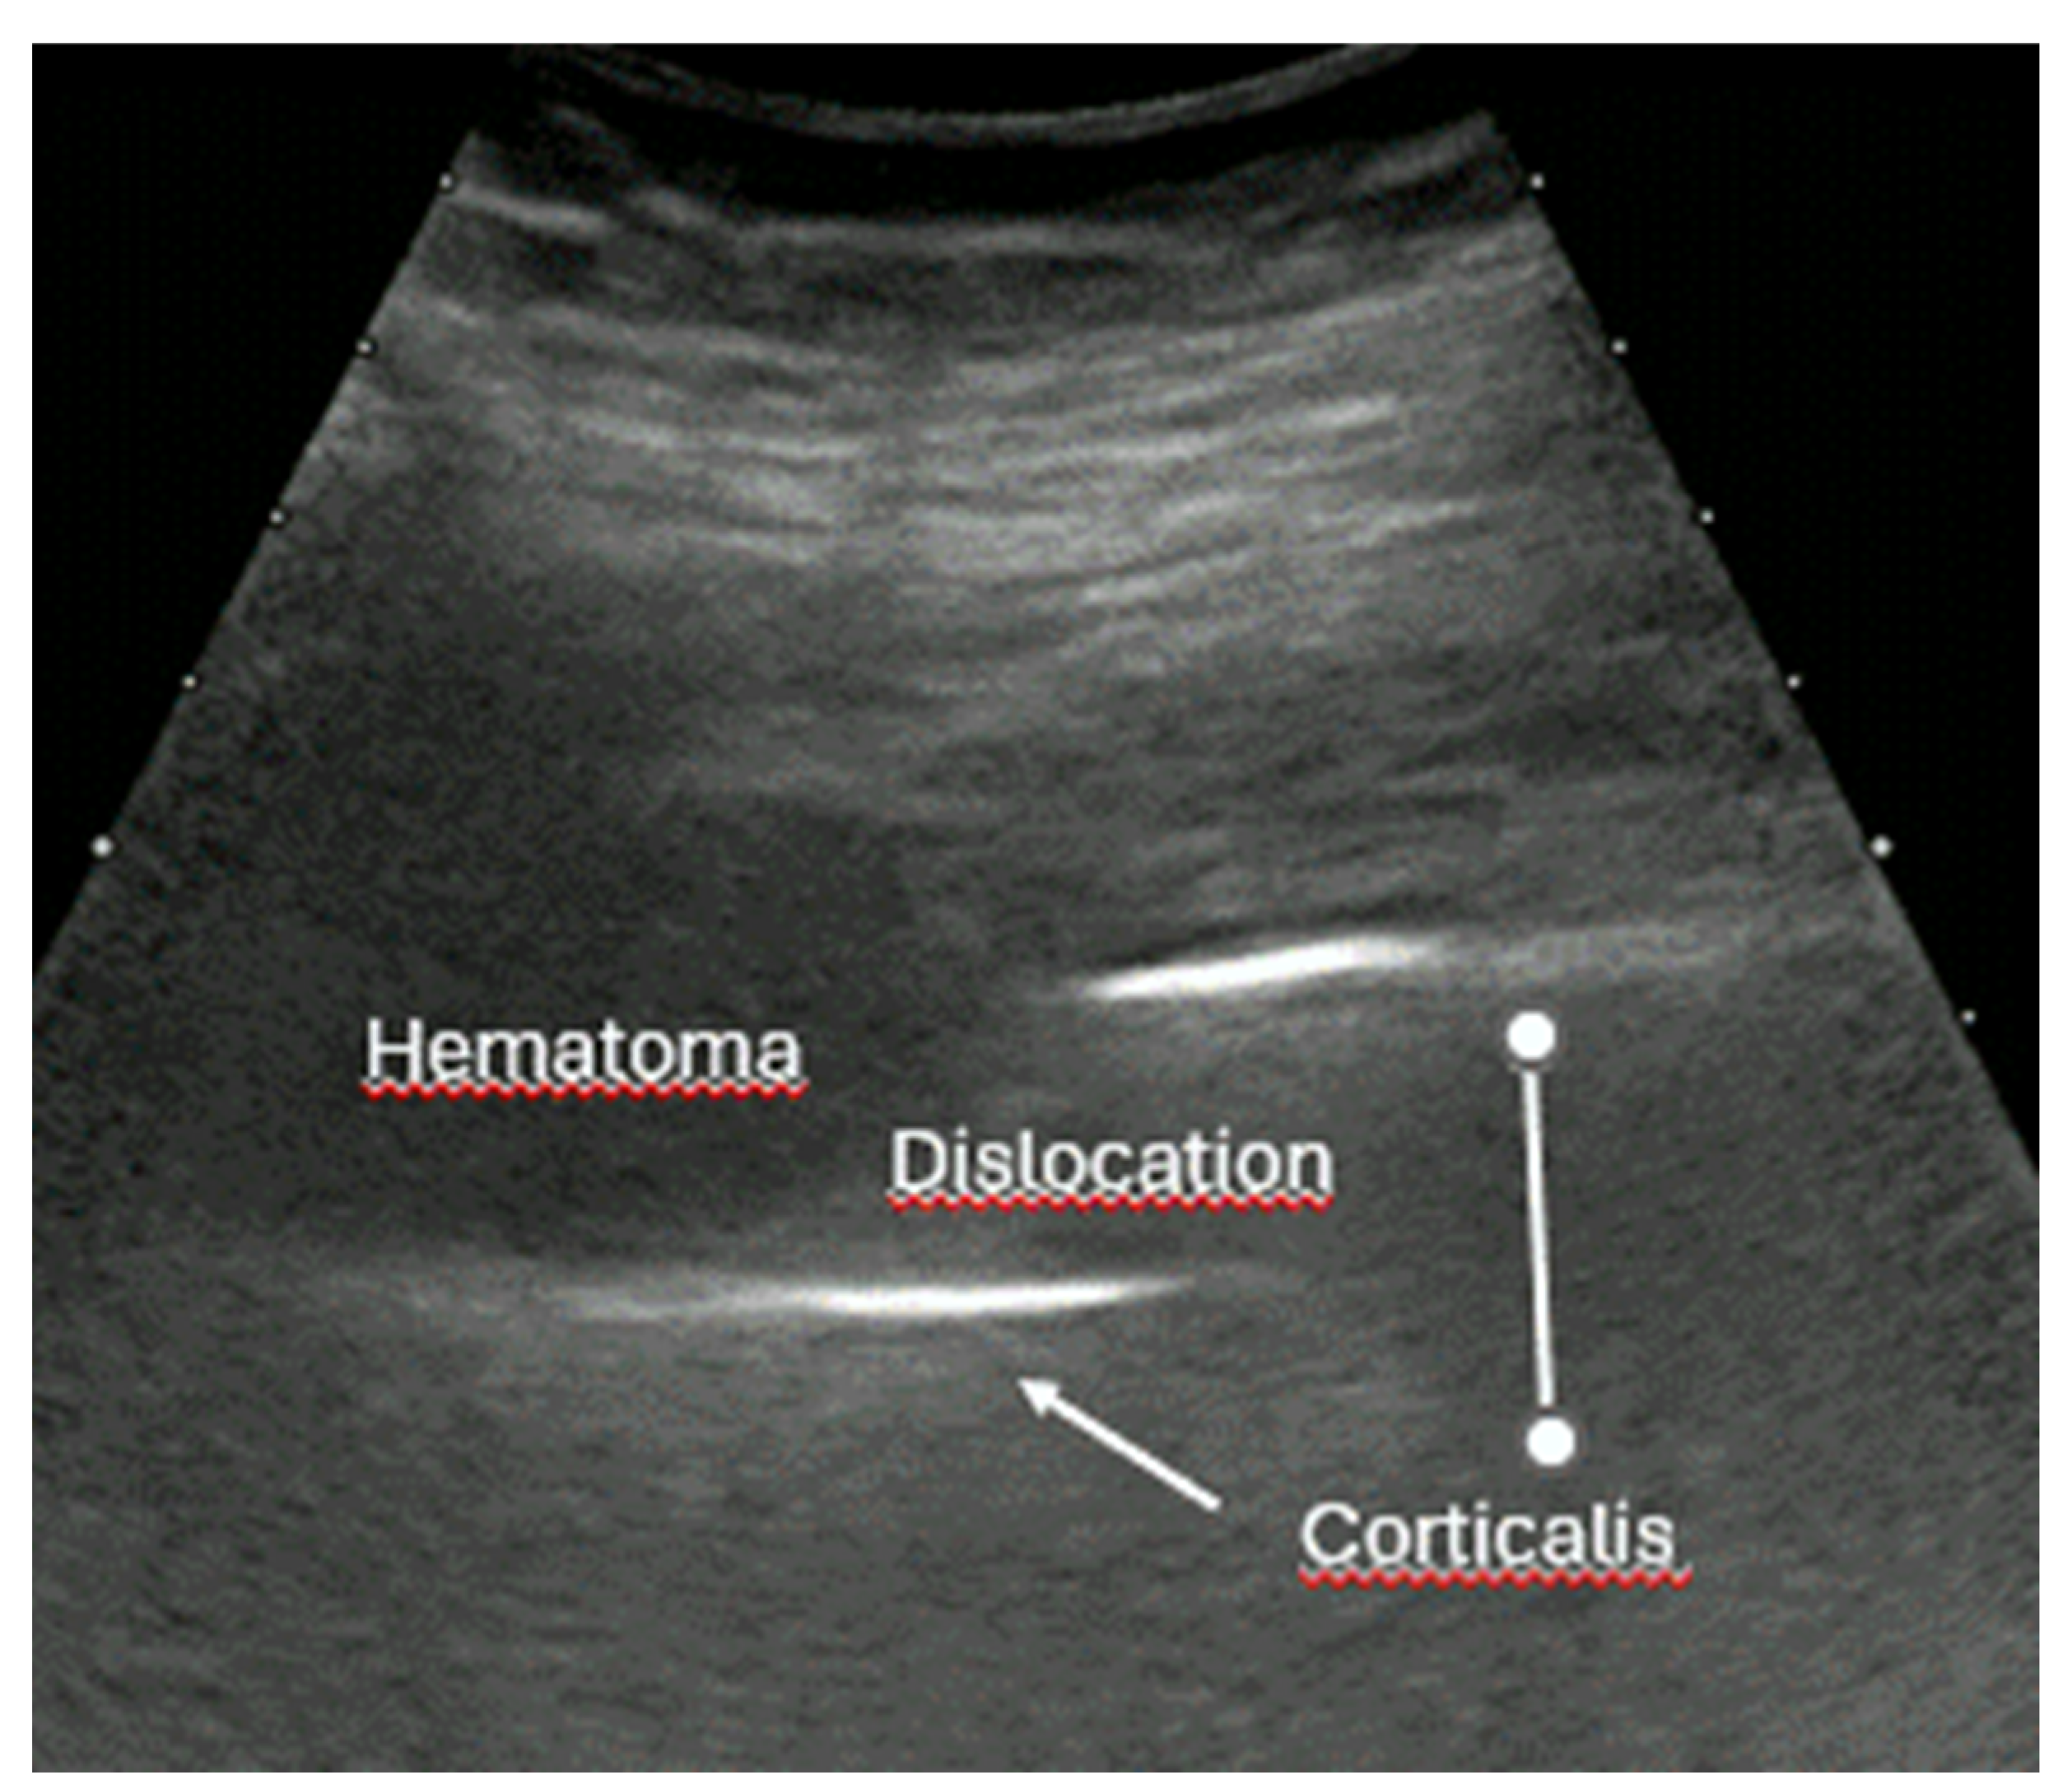

- Dislocation: misalignment of bone fragments, visible as separation or shift from their normal anatomical position.

- Local hematoma or soft tissue edema: fluid collections or increased echogenicity near the fracture site indicating bleeding and inflammation.

- Example: Hemorrhagic Shock Due to Distal Femur Fracture—Rapid Diagnosis via Ultrasound